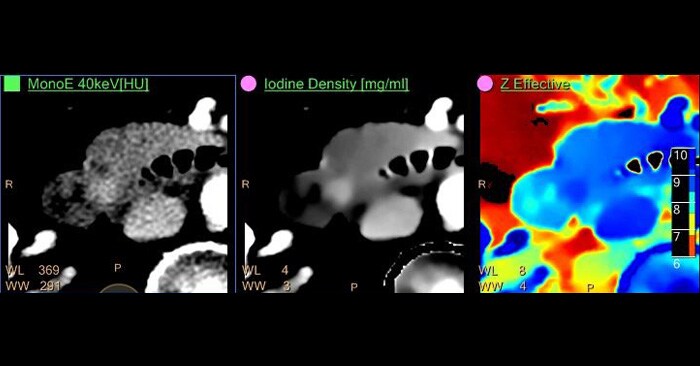

IQon Spectral CT consistently captures spectral information without special planning or set-up. In this case of a middle-aged female presenting to the ER complaining of abdominal pain, an abdomen/pelvis scan was ordered. The patient was scanned on the IQon Spectral CT.

Upon reviewing the conventional CT, the clinician noted that the pancreatic duct appeared to be dilated, but they could not identify the cause from the conventional images. The scan was immediately reviewed using Spectral Magic Glass, which allowed the radiologist to view five different spectral results without changing his workflow. Upon review of the various results, the clinician identified a lesion in the head of the pancreas and the patient was referred for an endoscopic ultrasound biopsy. That pathology report identified a tubular adenoma of the Ampulla of Vater.

Images courtesy of UCL Brussels, Belgium